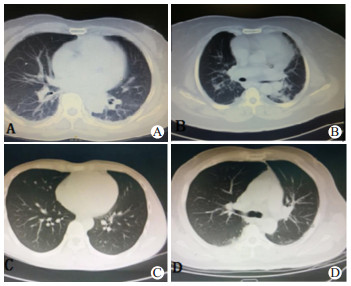

急性PQ中毒患者临床胸部CT显示,早期主要表现为肺纹理增粗、渗出实变和磨玻璃影; 中期主要表现为渗出实变、胸腔积液和间质改变; 晚期主要表现为渗出实变和间质改变[6]。比较入院首诊胸部CT显示,两组患者肺部CT出现肺纹理增粗、渗出实变和磨玻璃影等征象及肺CT阳性率均差异无统计学意义。比较两组患者中毒后72 h胸部CT结果,出现肺纹理增粗和磨玻璃影等征象及肺CT阳性率在组间差异有统计学意义,死亡组中毒后72 h出现渗出实变征象的比例明显高于存活组,但差异无统计学意义,见表 2和图 1。

| A:双肺纹理增粗伴磨玻璃影; B:双肺下野渗出实变伴少量胸腔积液; C:双肺下野轻度磨玻璃影; D:双肺下野少量渗出 图 1 急性百草枯中毒患者常见肺CT影像学表现 Fig 1 Common presentation of lung CT findings in PQ poisoning patients |